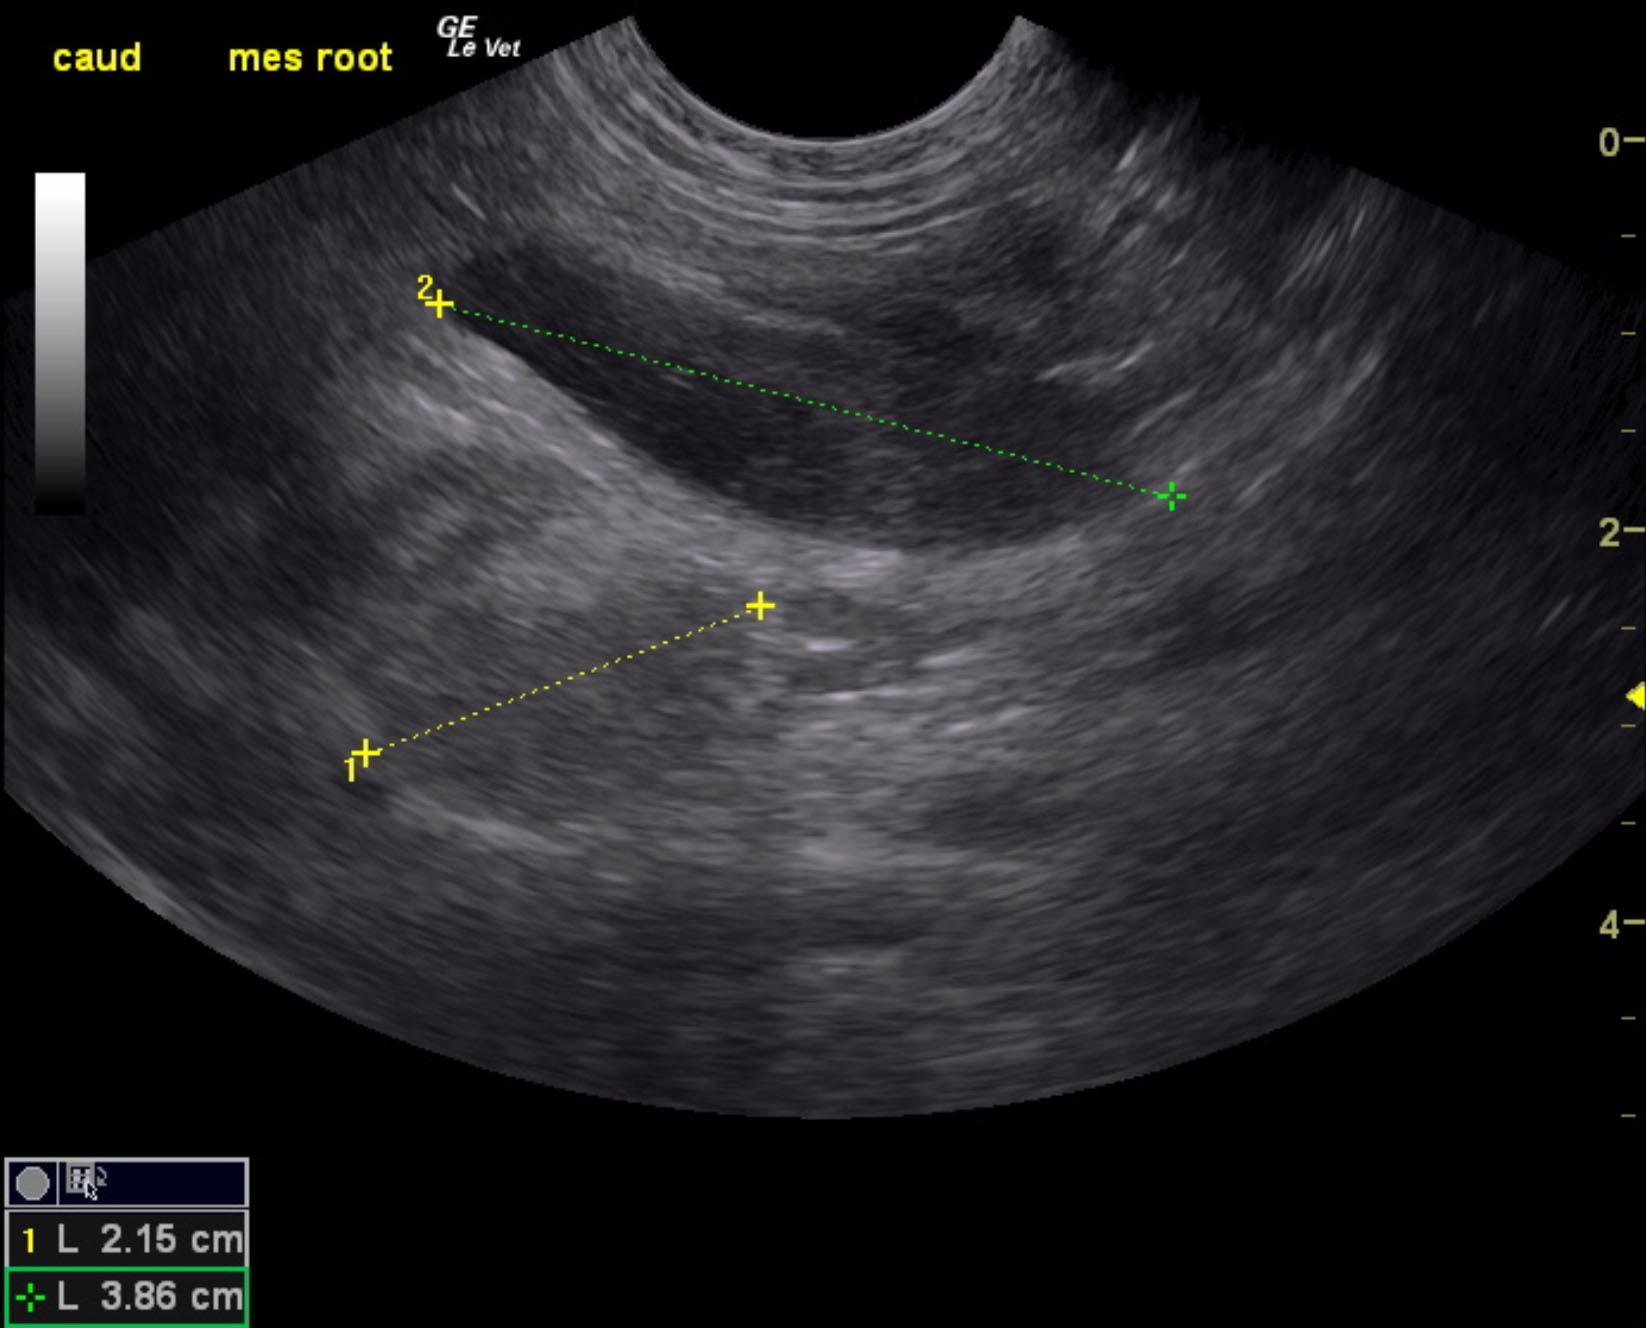

A 6-month-old intact male Labrador was presented for evaluation of diarrhea and vomiting for approximately 1 week and more recently only hemorrhagic diarrhea.

A 6-month-old intact male Labrador was presented for evaluation of diarrhea and vomiting for approximately 1 week and more recently only hemorrhagic diarrhea.